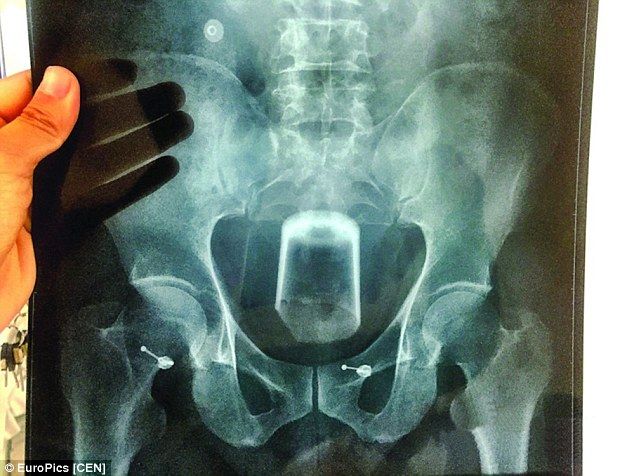

私がクラインを捕まえようとして、彼の上に倒れ掛かった。そのとき、クラインの背中からボンッとはじける音がした。

クラインは大声で叫んだ。そして液体が彼の肛門から流れ出したんだ」

目撃者によると、落下の衝撃と肛門内の圧力のためにシナモンロール缶が爆発したとのこと。

缶とその中身はクラインから取り除かれた。クラインは怪我の治療を受け、ラスベガス警察に拘留された。